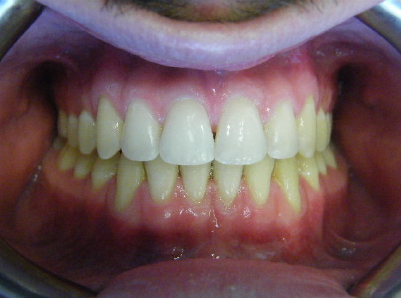

Patient 2: Significant increased overjet and upper and lower crowding.